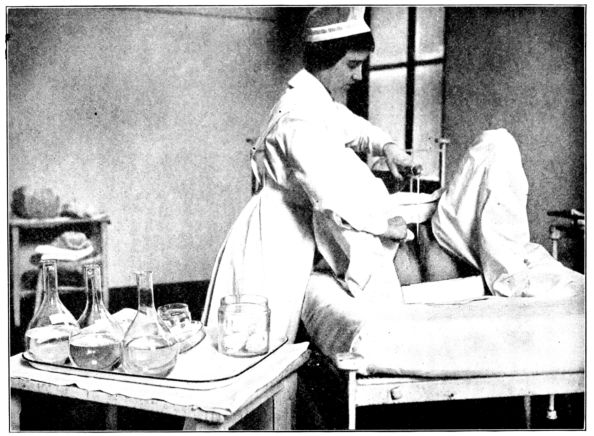

| 155. | Preparation for circumcision | 468 |

| 156. | Baby draped with sterile sheet, in above | 469 |